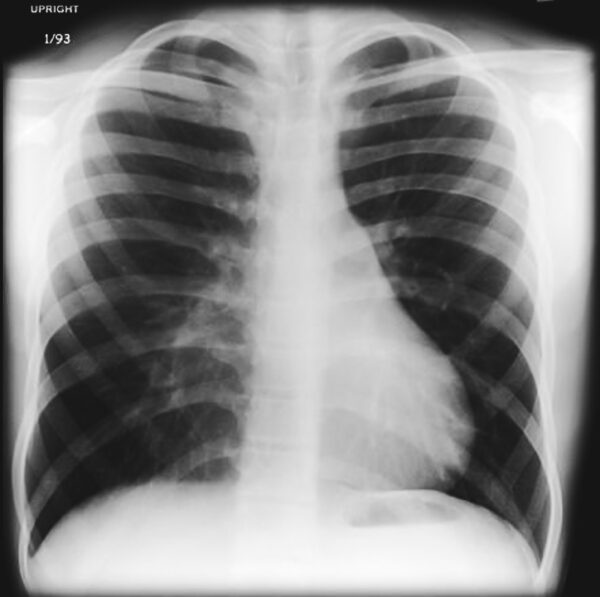

Pectus excavatum is a deformity of the chest in which the chest looks sunken or caved in. It occurs when the cartilage that holds the ribs to the breastbone has a defect and pushes the breastbone inward, leaving a deep dent in the centre of the chest between the pectoralis major muscles.

The cause of this chest deformity is unknown however it is more common among those with Down’s syndrome, Edwards syndrome, connective tissue disorders such as Marfan syndrome and those with homocystinuria or morquio.Pectus excavatum may be mild, moderate or severe and depending on each individual case, surgical repair may or may not be needed. For those who have more severe pectus excavatum the breastbone puts pressure on the heart and lungs, and the sunken chest creates issues with self-esteem and confidence, surgery may be needed to relieve the pressure and correct the deformity.